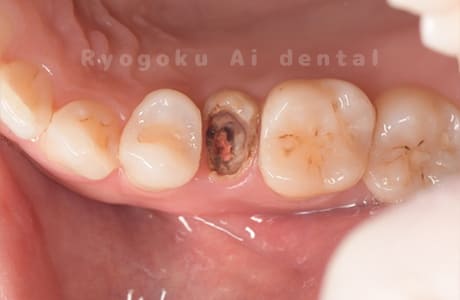

Case12

- 縁下カリエス

- 治療内容

- クラウンレングスニング、ジルコニアクラウン修復

- 治療費用

- 約220,000円

被せ物の中から臭いがするとのことで、被せ物を外したところ大きな虫歯となっていました。このまま被せてしまうと被せ物が外れやすいため、埋まっている歯を出すためのクラウンレングスニング処置を行い、その後、ジルコニアクラウンで被せ物を行いました。